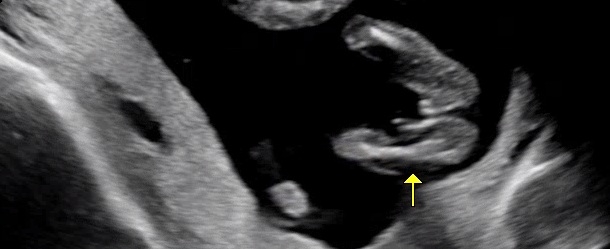

16주2일 성별 봐주세용

오늘 2차기형아 검사하면서 성별확인을 했는데요~~의사쌤이 딸이네요~했는데 집에와서 다시 보니 왜케 가운데 뭐가 있는것 같죵?🤣딸맞을까용?